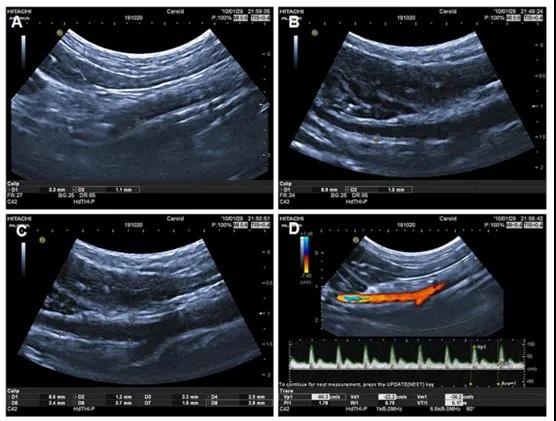

ApoE 纯合突变犬颈动脉动脉粥样硬化斑块及血流动力学VDU超声影像图

近日,首都医科大学宣武医院血管超声诊断科主任华扬研究组与北京希诺谷生物科技公司,通力合作于Atherosclerosis Plus发表了题为“Identification of the atherosclerosis phenotype in vivo by vascular duplex ultrasonography in ApoE deficient dogs”的研究论文,通过ApoE 基因编辑犬这一大动物模型,展示了血管双功超声(VDU)是一种用于评估大动物模型动脉粥样硬化表型的最佳体内非侵入性方法。合作团队利用血脂分析揭示ApoE基因编辑纯合犬的甘油三酯、总胆固醇和低密度脂蛋白水平均显著高于野生对照和ApoE基因编辑杂合犬。通过VDU诊断,揭示ApoE纯合犬的颈总动脉和主动脉的内中膜厚度显著增加、动脉粥样硬化的发生率显著高于ApoE杂合犬,且发生时间更早。组织病理学证实,ApoE纯合犬的主动脉、颈动脉和髂总动脉均存在显著的动脉粥样硬化病变。本研究通过血脂分析、VDU诊断、组织病理学分析等多学科交叉的方法揭示了Apoe基因编辑犬动脉粥样硬化分布模式的特征以及随着年龄增长的内、中膜厚度变化,为在大型动物模型中评价动脉粥样硬化表型提供了一种体内无创方法,同时为进一步应用该模型提供了相关基础数据。该研究的发表,证实ApoE基因编辑犬为开发可靠的危险分层分子标志物的影像学检测以及临床用药有效性检测提供动物模型保障,可极大的提高相关研究的临床转化效率。